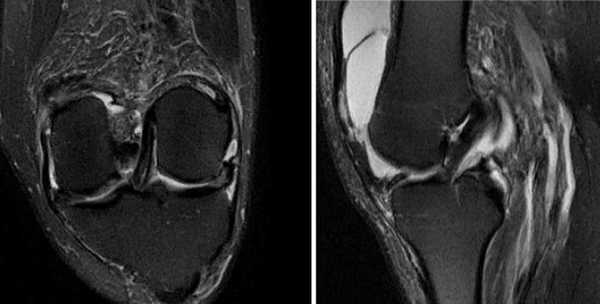

Глубокий инфрапателлярный бурсит

Воспаление глубокой поднадколенниковой сумки на МР-скане (стрелка)

На МРТ глубокий инфрапателлярный бурсит проявляется в виде треугольного скопления жидкости сзади сухожилия надколенника. При обнаружении у подростков воспаленную сумку дифференцируют от болезни Осгуда-Шлаттера, для которой типичны гиперинтенсивность сигнала. Инфрапателлярный бурсит чаще развивается при падении на колени. Патологии подвержены плиточники, строители, горничные.